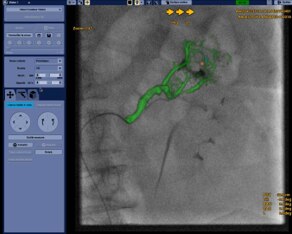

Guider